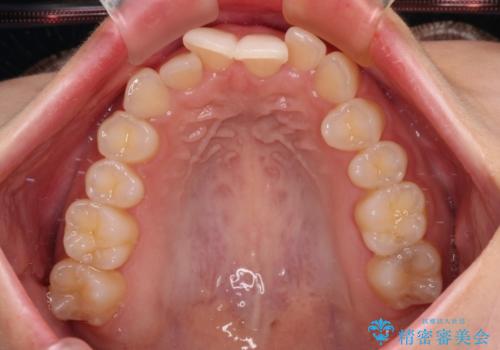

前歯が隠れるほどのデコボコをインビザライン矯正できれいに整える

- 前歯のデコボコを気にして来院された患者様です。

全体的にデコボコが多く、特に下の前歯は隠れてしまうほどの状態でした。

左右ともに奥歯の咬み合わせが理想的な位置にあったこともあり、患者様のご希望通り、インビザラインにて矯正治療を行うこととしました。

マウスピース矯正特有の、奥歯が噛みにくくなるという現象の解消に少し期間をいただきましたが、日々の装着時間を遵守していただき、綺麗な歯列に整えることができました。